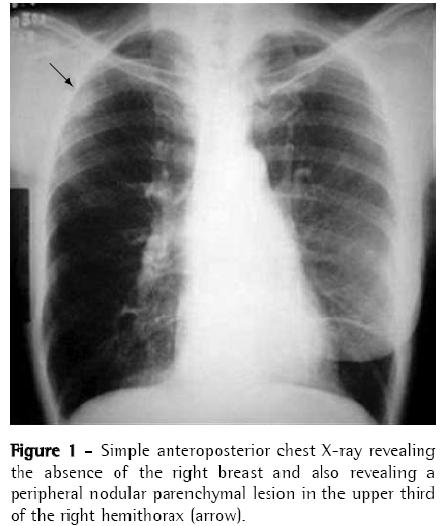

A 60-year-old Caucasian female who had been in menopause for 14 years was referred to the Department of Oncology due to the presence of a pulmonary nodule on chest X-ray (Figure 1) diagnosed in the postoperative follow-up evaluation of breast cancer.

The patient then underwent computed tomography of the chest, which revealed a pleural, parenchymal pulmonary nodule measuring approximately 30 × 25 mm (Figure 2) in the right lung. Therefore, a hypothetical diagnosis of pulmonary metastasis of the breast carcinoma previously removed was made, and biopsy was indicated for diagnostic confirmation.